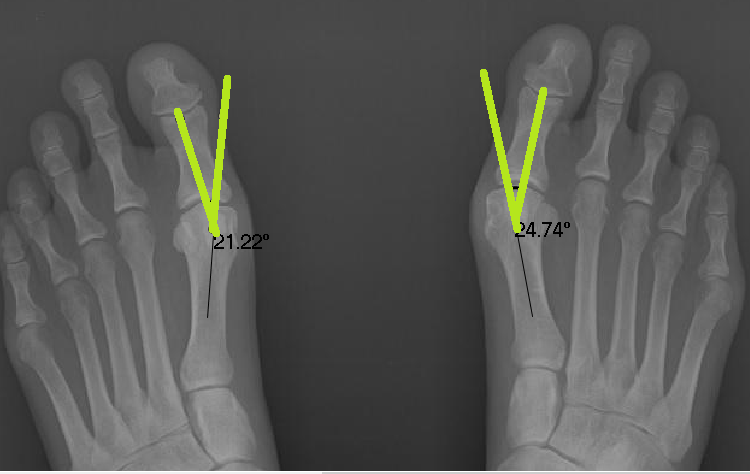

Below is a patient who has completed a short course of Foot Mobilisation Therapy here at Corrective Foot Solutions.Before the treatment the bunion angles are 21.22 and 24.74 degrees. Normal angles are between 12-15 degrees.

Post treatment angles are 14.8 and 13.3 degrees- a significant change of 11 and 7 degrees. NO surgery required and a happy patient!